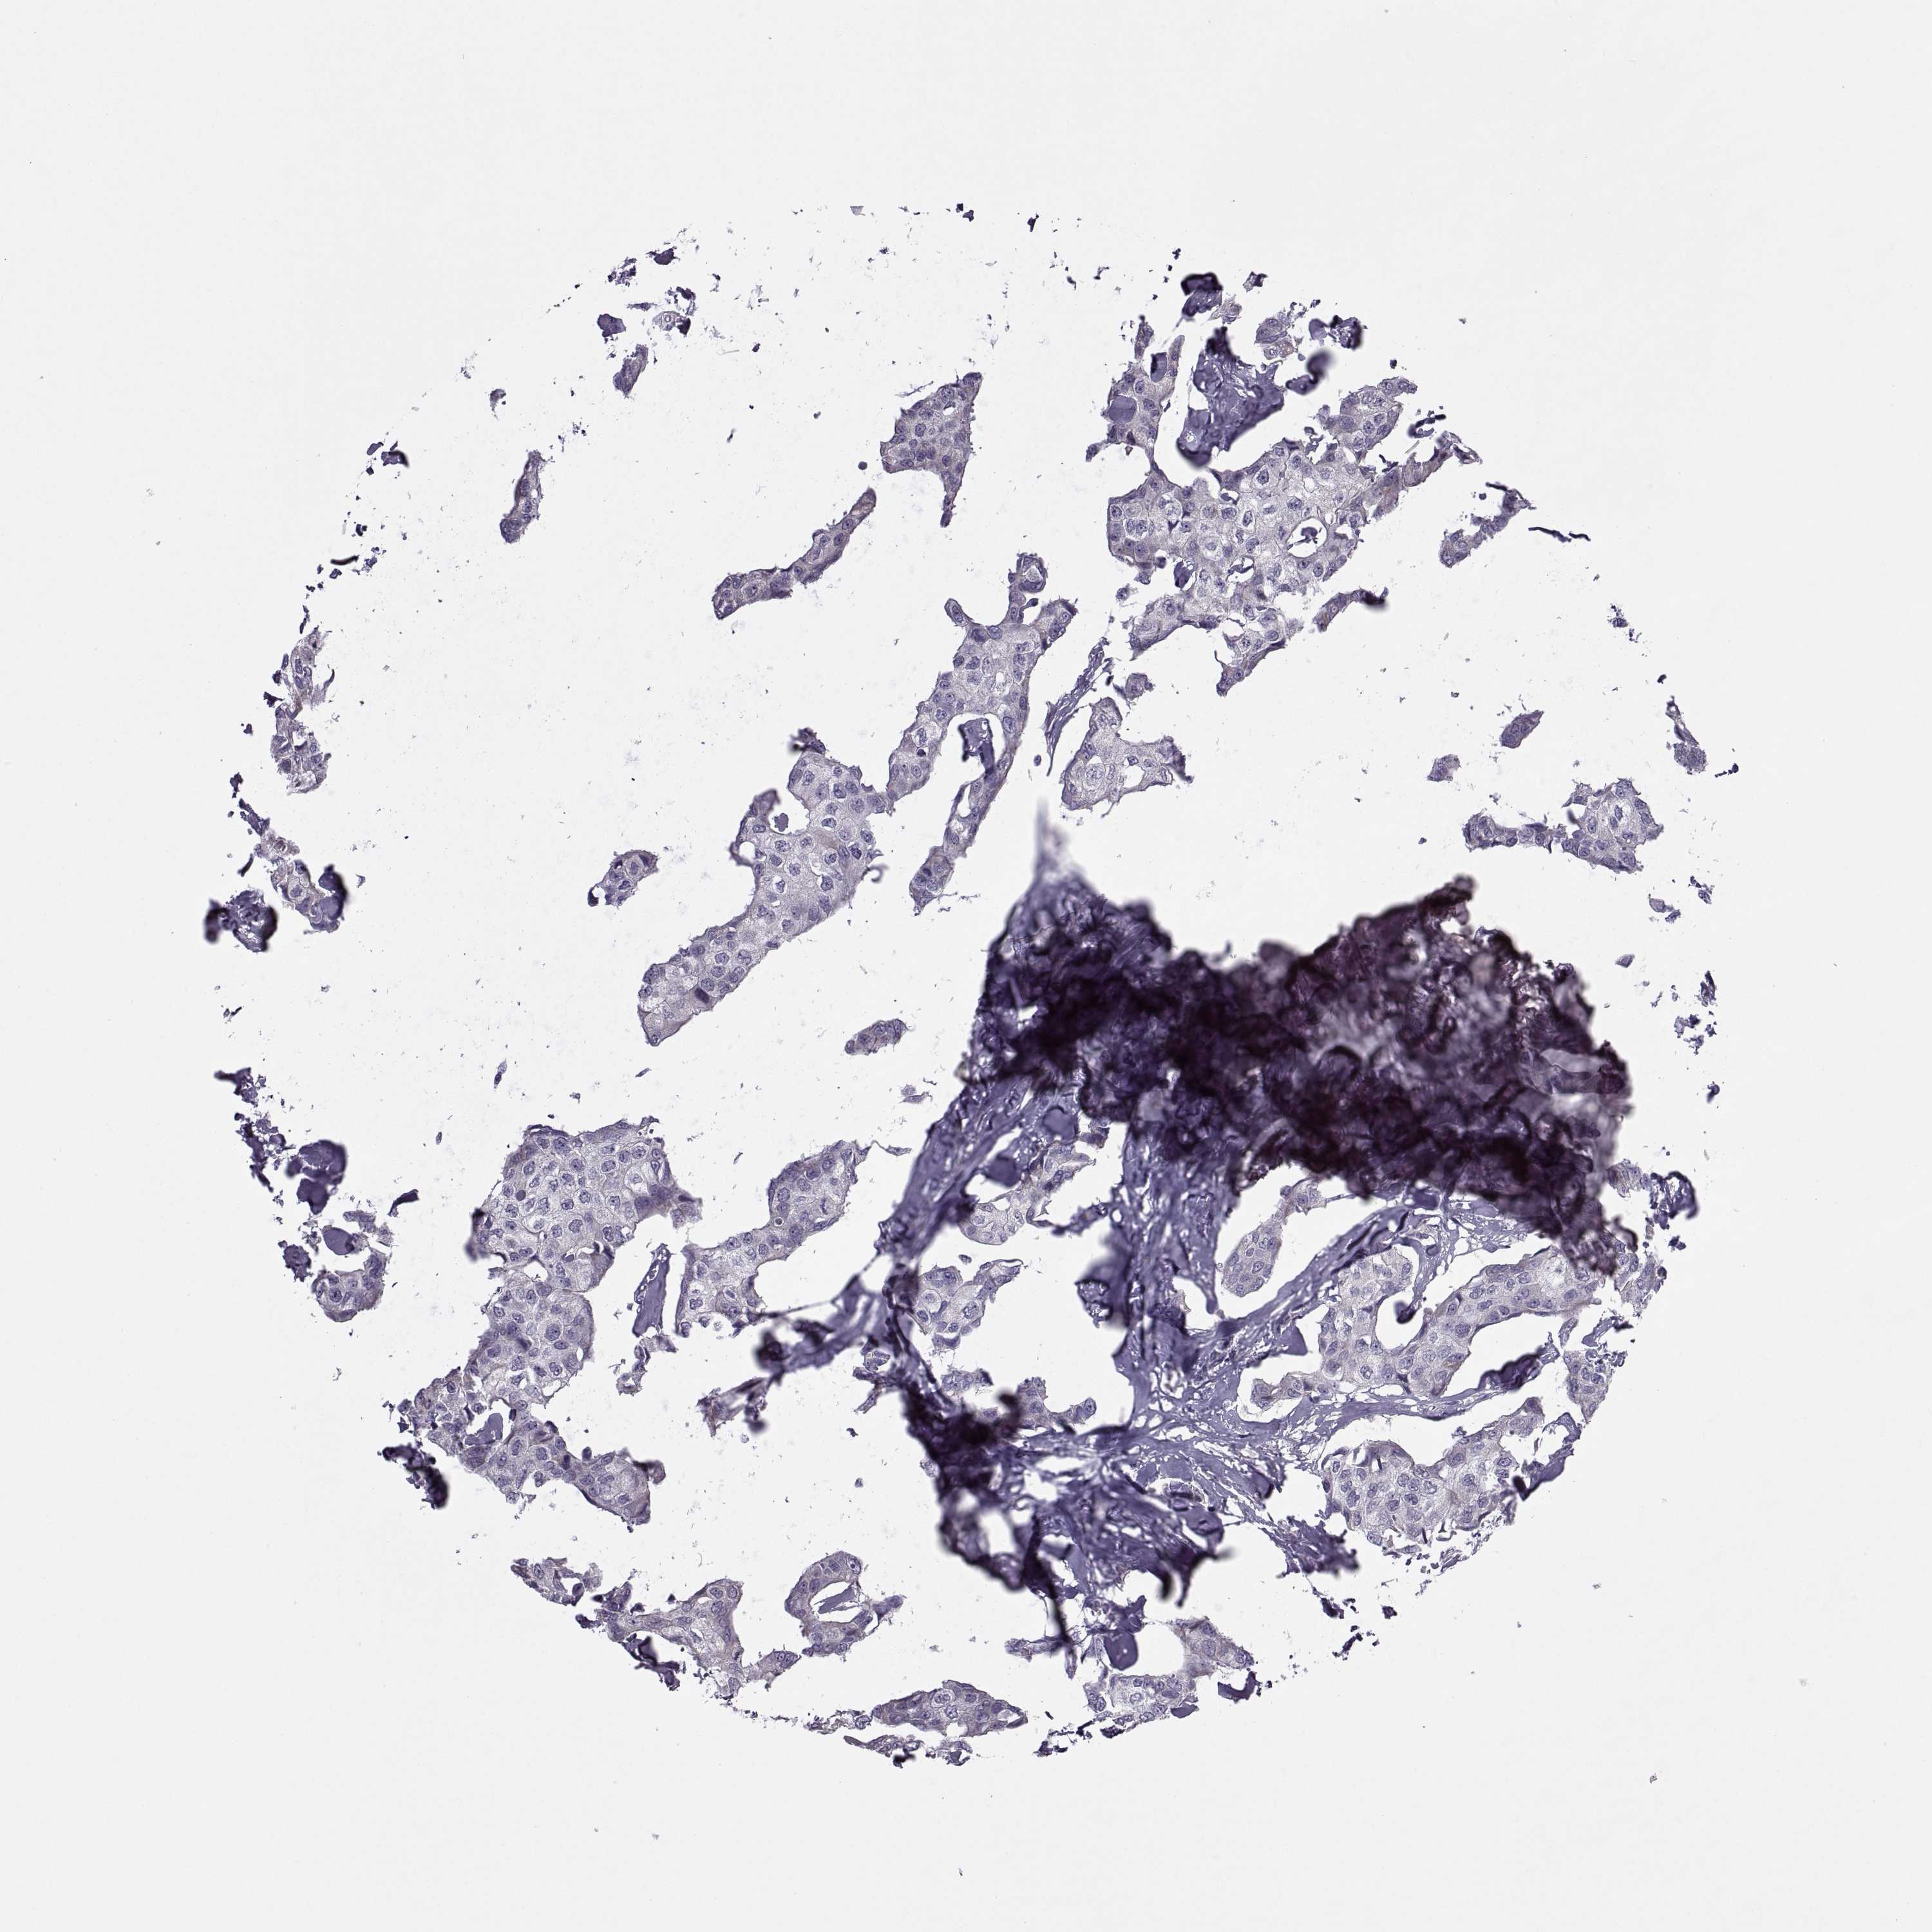

Breast cancer

Human cancer

Breast invasive carcinoma